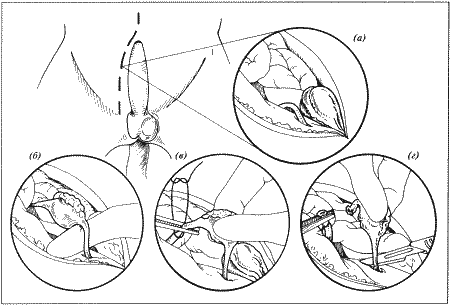

Вагинальная эндоскопия

Прекращение секреции эстрадиола фолликулами и переход их к секреции прогестерона приводят к снижению как отечности, так и васкуляризации слизистых оболочек, что сопровождается выраженным изменением характера вагинальных выделений, выявляемым с помощью вагинальной эндоскопии. На стадии проэструса слизистая оболочка становится более выпуклой и отечной, затем наблюдается ее уменьшение; по мере приближения овуляторного пика слизистая сжимается и бледнеет, в некоторых случаях становясь практически белой (фиг. 1.1). Перечисленные изменения свидетельствуют о приближении стадии, характеризующейся постепенным повышением концентрации прогестерона перед овуляцией и последующим наступлением фертильного периода. Эти изменения легко узнать, имея даже небольшую практику (фиг. 1.3), кроме того, они настолько воспроизводимы, что по набору признаков их можно оценивать полуколичественно. Вагинальная эндоскопия весьма полезна в определении оптимальных сроков вязки. По окончании фертильного периода, т. е. в начале метэструса — слизистая оболочка влагалища бледнеет и истончается, складки становятся закругленными — и что, вероятно, является наиболее характерным признаком, — слизистая в переднем отделе влагалища выглядит раздраженной и при прикосновении быстро сжимается, образуя розетку.

Фиг. 1.3.

Эндоскопическое исследование слизистой влагалища. Динамика изменений на протяжении цикла: (а) проэтрус — розовая окраска и отечность; (b) начало эструса — слизистая бледнеет, отек начинает уменьшаться (обычно перед пиком ЛГ); (c) середина эструса — слизистая бледная, уменьшение отека (сморщивание) явно выражено, что соответствует середине фертильного периода; (d) начало метэструса — видны закругленные складки, при прикосновении слизистая смыкается, образуя розетку (е) (см. Приложение)